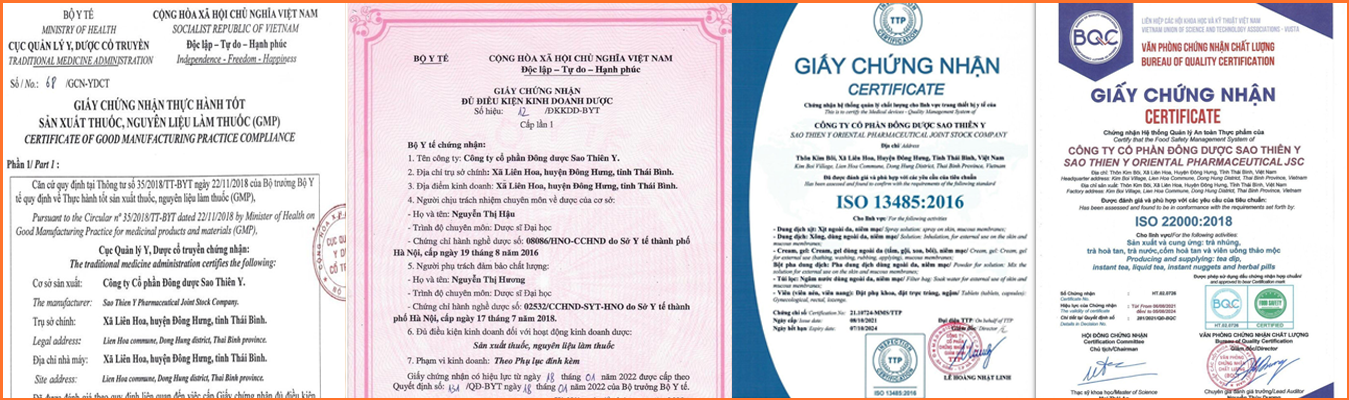

Certificate of eligibility for pharmaceutical business

Certificate of eligibility for pharmaceutical business

Certificate of Good Manufacturing Practice for Medicines and Pharmaceutical Materials (GMP)

Certificate of Good Manufacturing Practice for Medicines and Pharmaceutical Materials (GMP)

This is to certify the Medical devices - Quality Management System

This is to certify the Medical devices - Quality Management System

Certificate of eligibility for cosmetic production

Certificate of eligibility for cosmetic production

Certify that the Food Safety Management System

Certify that the Food Safety Management System